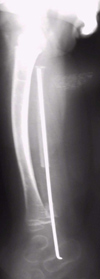

Tale lesione richiede l'effettuazione di una resezione chirurgica del perone con sintesi endomidollare (Figura�2).

Figura 2. Sintesi endomidollare del perone.